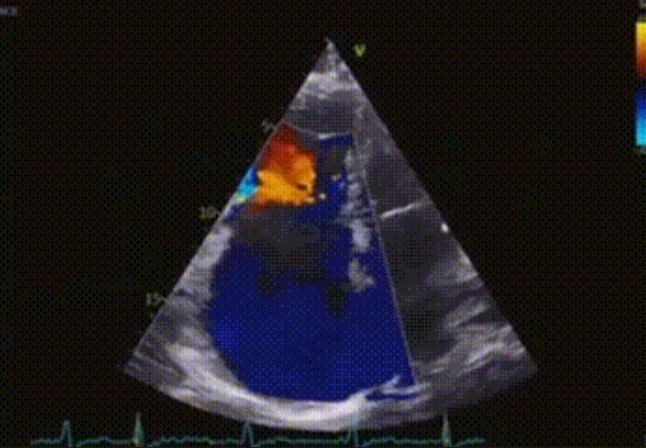

術(shù)前心臟超聲提示:極重度三尖瓣返流,右房容積明顯增大,三尖瓣瓣環(huán)顯著擴(kuò)張。

術(shù)后心臟超聲提示:LuX-Valve Plus植入后,三尖瓣瓣環(huán)處可見人工瓣膜回聲,未見返流,人工瓣膜穩(wěn)定,瓣葉開閉良好,連續(xù)多普勒估測(cè)三尖瓣平均跨瓣壓差僅為1mmHg。